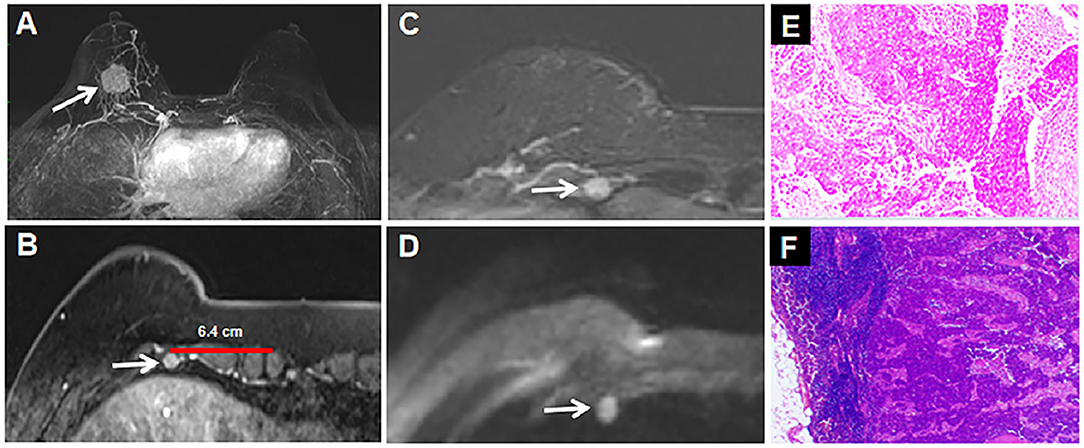

Learn how to detect your swollen lymph nodes and how to talk. A Retrospective Analysis On Metastatic Rate Of The Internal Mammary Lymph Node And Its Clinical Significance In Adjuvant Radiotherapy Of Breast Cancer Patients Bmc Cancer Full Text